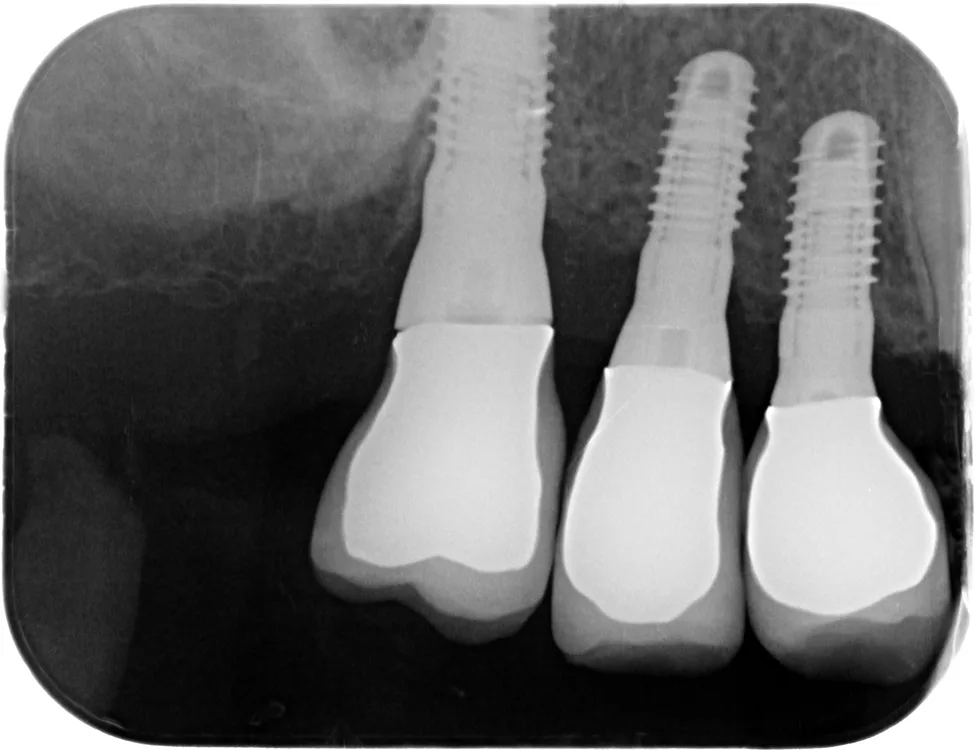

- Anatomische Information: Mehrinformationen sind die Nähe zum N. alveolaris, die Ausdehnung der Kieferhöhle und ihrer Septen, der Verlauf (insbesondere transversal) und die Mineralisation des Implantatknochens (nach Zahnextraktion) sowie die Positionierung des/r Implantate/s in Relation zu Nachbarzähnen (Abb. 9 und 10). Durch Schrägmessungen resultieren auch im DVT-Messfehler von bis zu 1 mm [5,6].

Implantatabstände

Wird ein Implantat neben einen natürlichen Zahn gesetzt, hat dies keine Auswirkungen auf die Interdentalpapille. Setzt man zwei Implantate nebeneinander, geht unabhängig vom verwendeten Implantattyp die suprakrestale biologische Breite und damit die Papille verloren [7]. Die Effekte von Implantaten mit Platform-Switching, konkavem Abutment, mikromaschiniertem Hals oder von Mikrobewegungen des Implantat-Abutments auf die Stabilität von krestalem Knochen und Weichgewebe beschränken sich auf subklinische Effekte [8,9]. Die chirurgischen Implantatabstände folgen daher primär den prothetischen Erfordernissen, insbesondere der Gegenbezahnung [10].

Im Idealfall gelten folgende Gesetze:

- Mindestabstand bei einwurzeligen Zähnen einschl. Prämolaren: 7 mm.

- Im Molarenbereich Implantatabstände von mindestens 11 mm (Abb. 11).

Häufig ist für die prothetisch ideale Implantatposition die lokale Knochenanatomie unzureichend, insbesondere bei Kreuzbiss oder langjährigen parodontalen Schäden usw. (Abb. 12 bis 14). Bestätigt die klinische Untersuchung diesen Verdacht, erfolgt eine 3D-Beurteilung der Knochenbreite mit individualisierter Implantatposition, ggfs. auch unter Verwendung durchmesserreduzierter Implantate. Alternativen Aufwand, Umfang und Kosten von Augmentation, Knochenentnahme oder Fremdmaterial mit Lappenmobilisation und möglicher Infektion vorab kalkulieren.